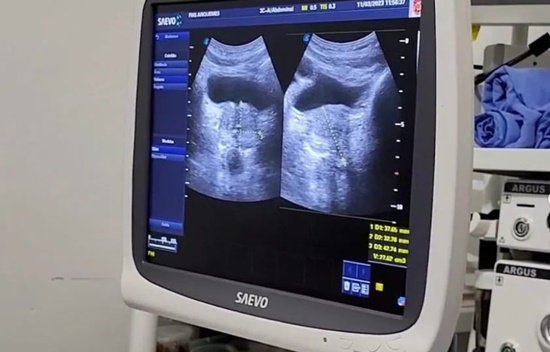

A Prefeitura de Ariquemes, através da Secretaria Municipal de Saúde - SEMSAU, realizou nos dias 25 e 26 (sábado e domingo), mais um mutirão de atendimentos para diminuir a fila de espera de pacientes que precisam realizar exames de ultrassonografia.

A ação aconteceu no Centro de Apoio Diagnóstico - CAD (em anexo do Hospital Municipal). Deste vez, 208 pessoas foram atendidas com ultrassonografias de abdome, tireoide, e transvaginal.